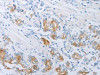

Applications: ELISA, WB, IHC

Tested Applications: ELISA, WB, IHC;ELISA:1:2000-1:10000, WB:1:500-1:2000, IHC:1:25-1:100

Dilution Ratio3: IHC:1:25-1:100